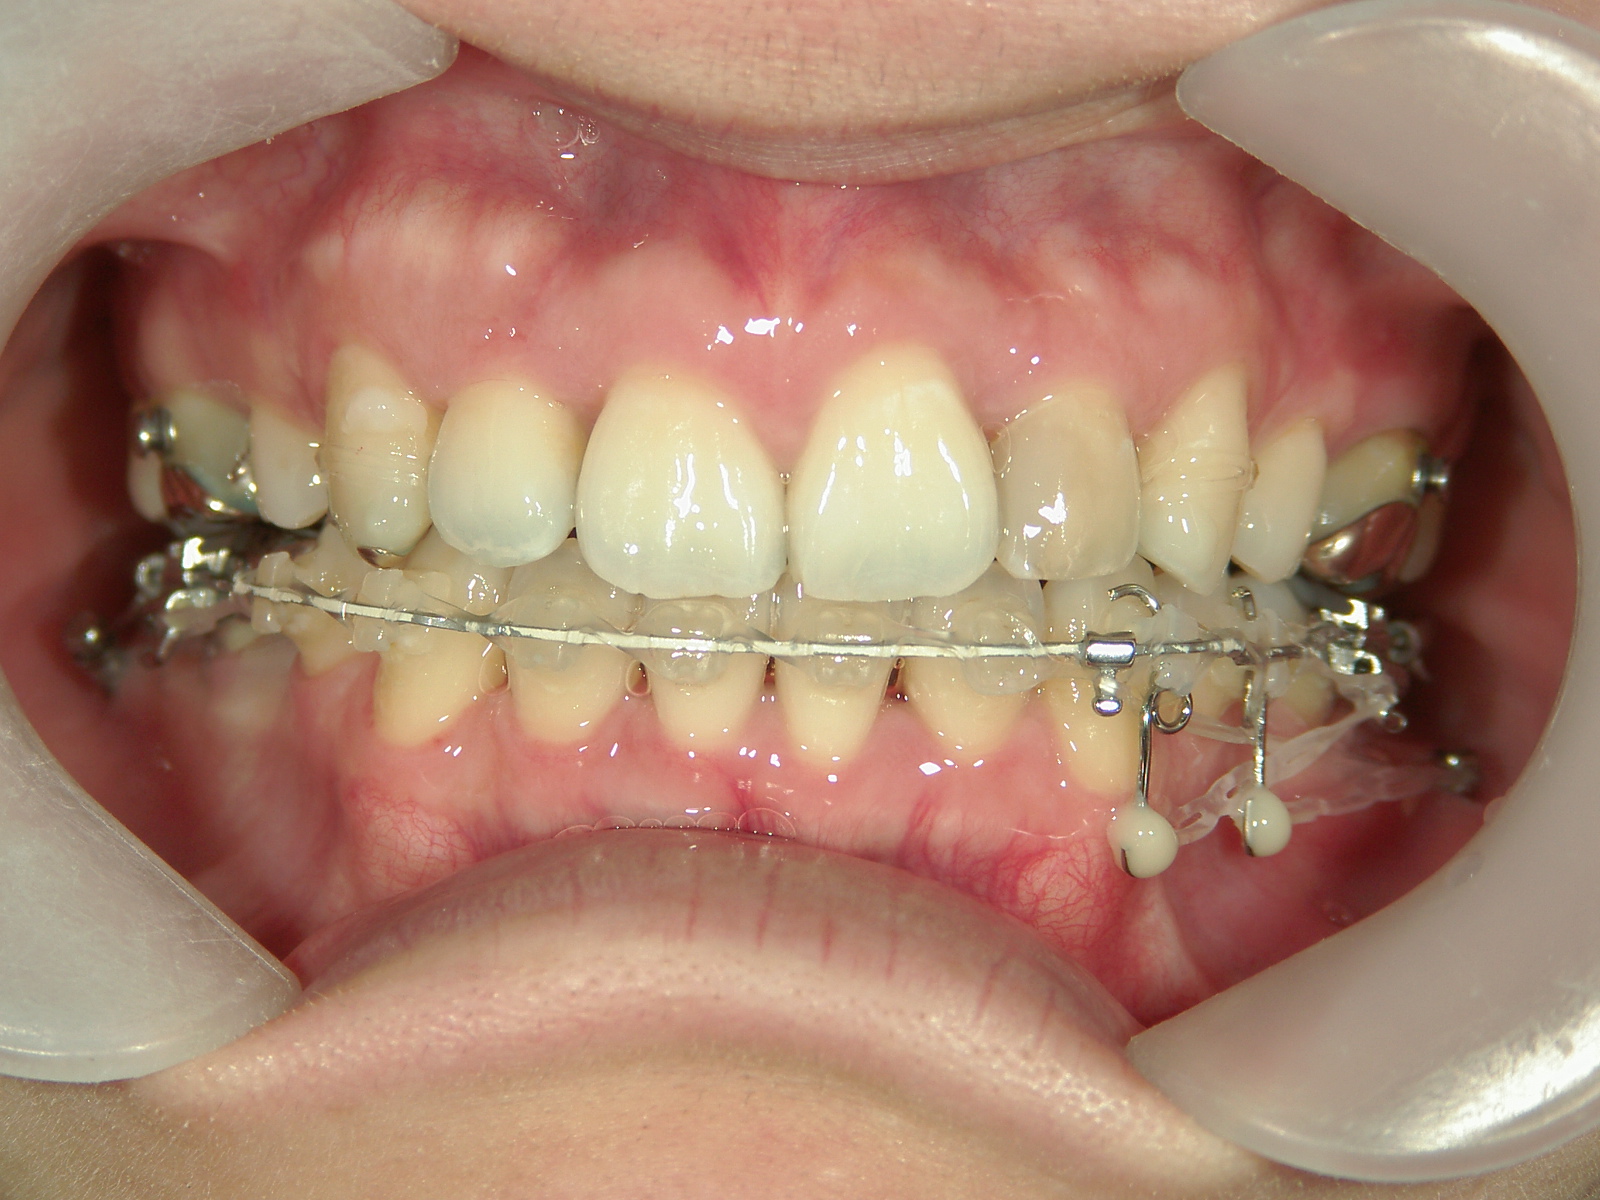

左右上 第一小臼歯(2本)、左右下 第二小臼歯(2本)を抜歯。

矯正装置(BH・QH)を併用。

ミニインプラント、アップライトスプリングを併用。

右下大臼歯(2本)をZ冠、E-MAX(On)に変更。